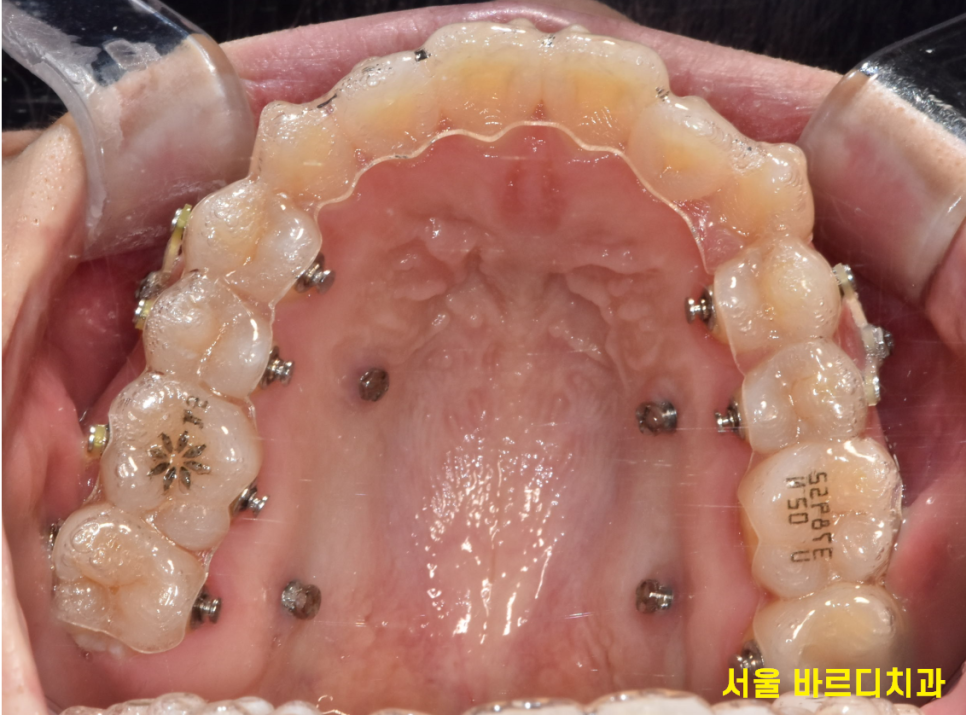

230909

그럼 투명교정이 군인분들에게 왜 좋은 선택인지,

구체적으로 살펴보겠습니다!!

- 최소화된 내원 횟수,

군인의 휴가를 고려한 편리함

인비절라인 장치와 같은 투명교정은

다른 교정장치에 비해 긴 시간을 두고 치과에 방문합니다.

장치를 보통 6~8주 단위로 바꿔 착용하거든요.